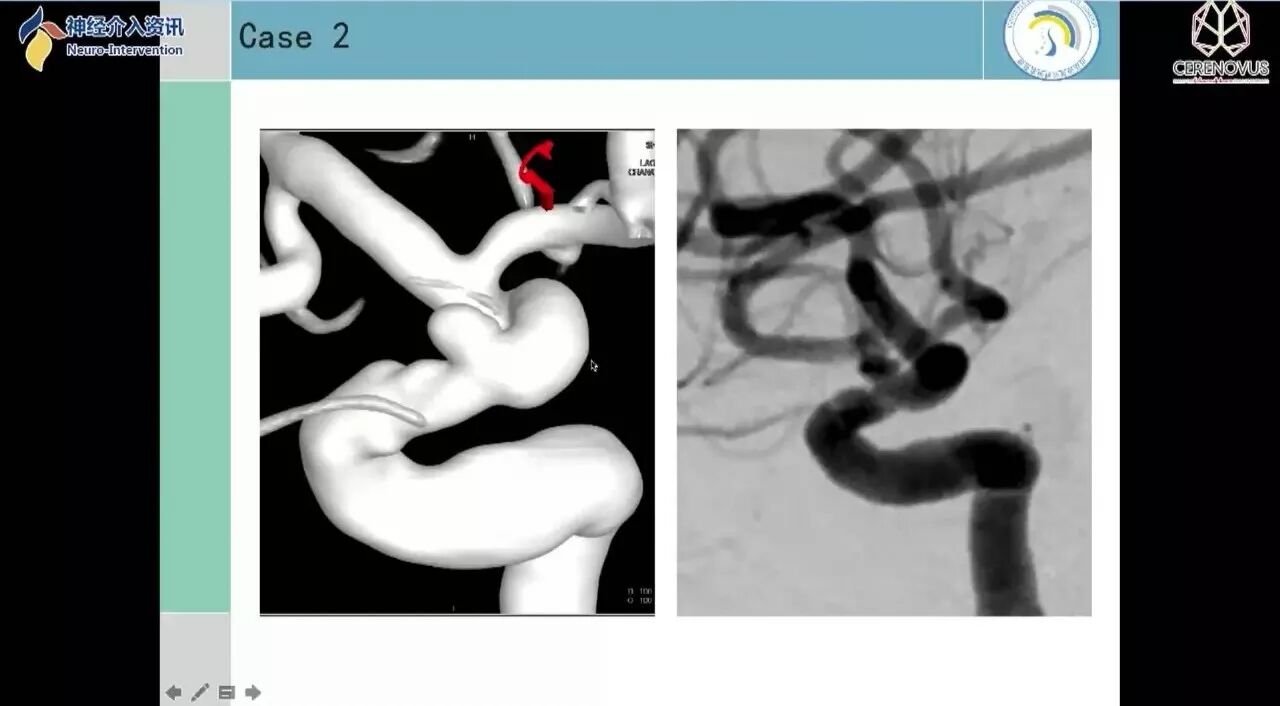

Galaxy弹簧圈在小动脉瘤栓塞术中的应用